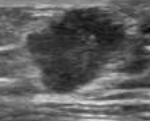

Υπερηχογράφημα ανδρικού μαστού. Πορογενές καρκίνωμα (Ευγενική παραχώρηση Dr. V. Penopoulos)